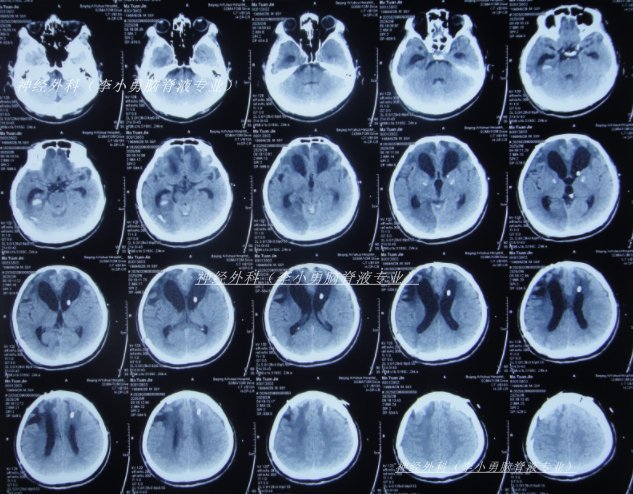

住院治疗1月零23天即2025年3月27日,查头颅CT和肺部(图-19)示感染大幅度好转。

图-19:2025年3月27日头颅肺部CT

继续治疗1月半脑脊液各项化验达标后于2025年6月3日,进行了脑室腹腔分流术(图-21)。

图-21:2025年6月4日头颅CT